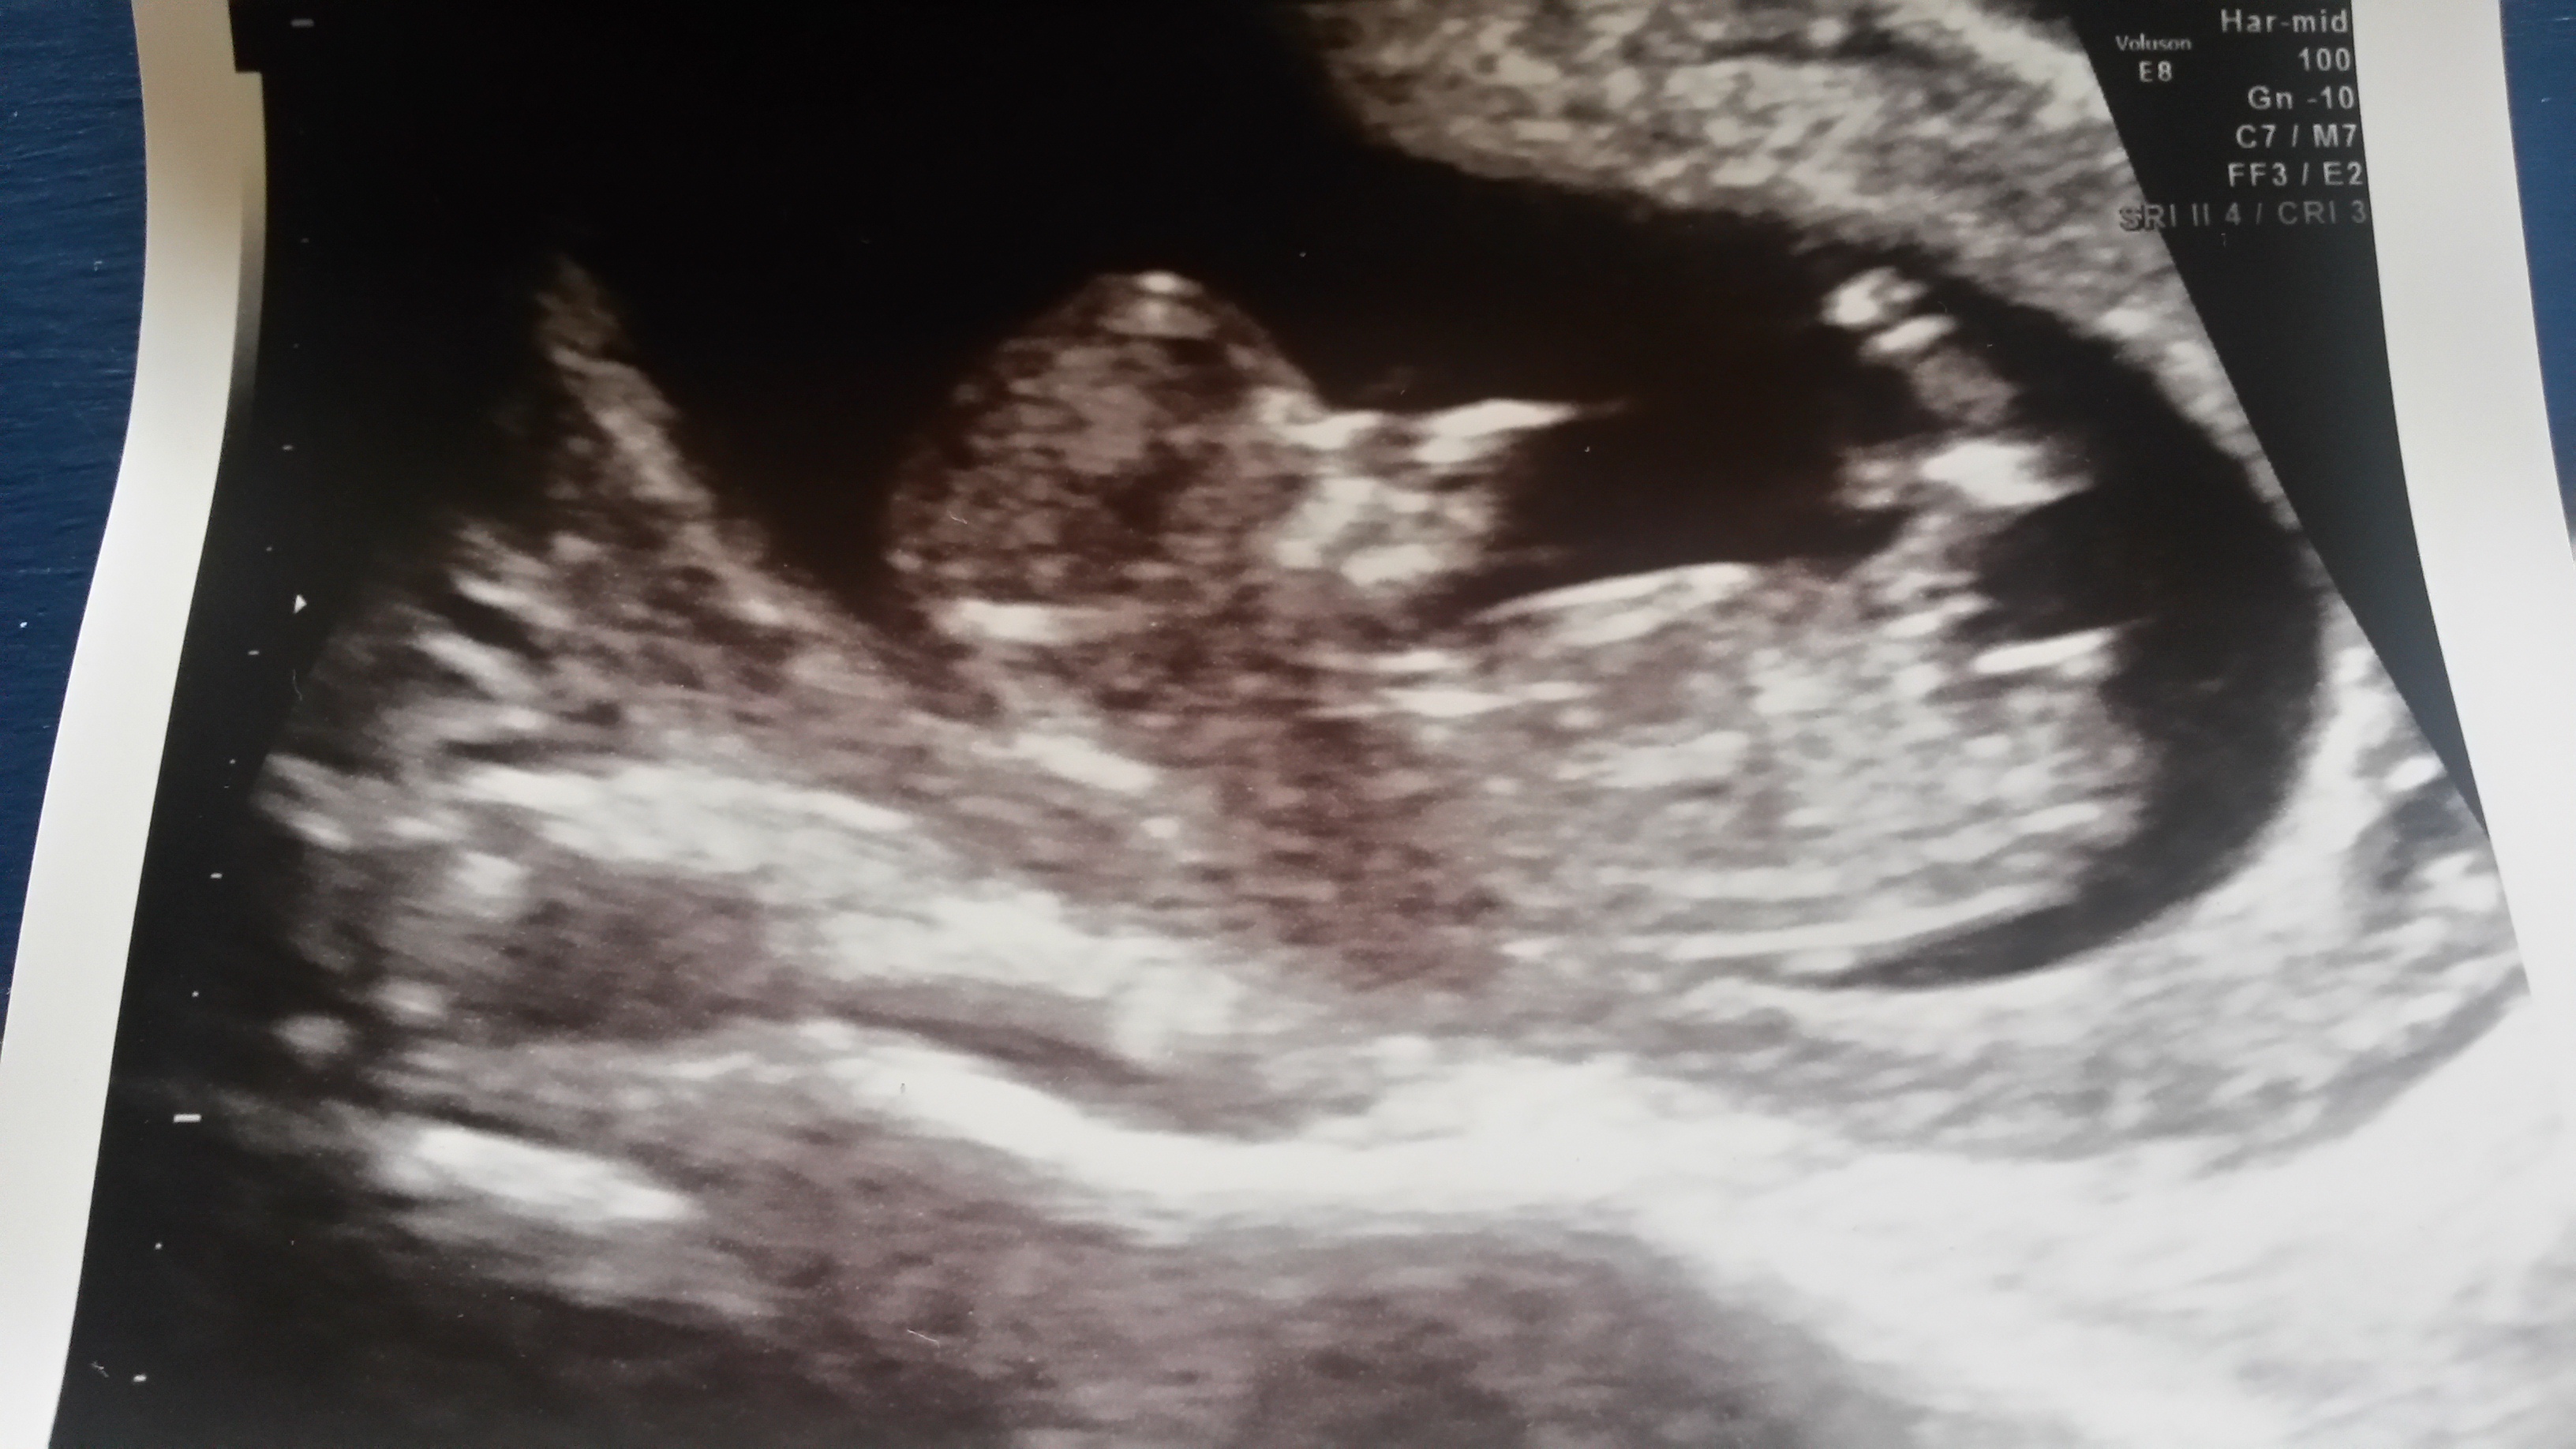

Any guesses? 12 w 4 days